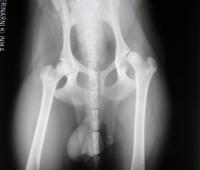

| Chovnost: | Zdraví: | ||